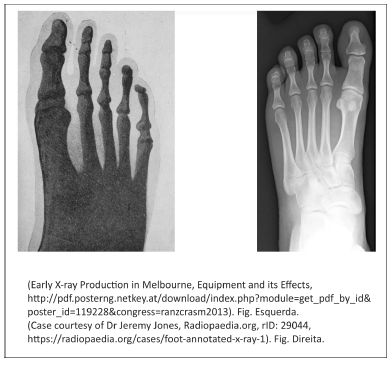

A figura da esquerda representa a primeira radiografia obtida na Austrália, em 1896, usando um tubo de raios catódicos de Crookes. A radiografia da direita é mais recente e evidencia a diferença de qualidade de imagem que se obtém hoje.